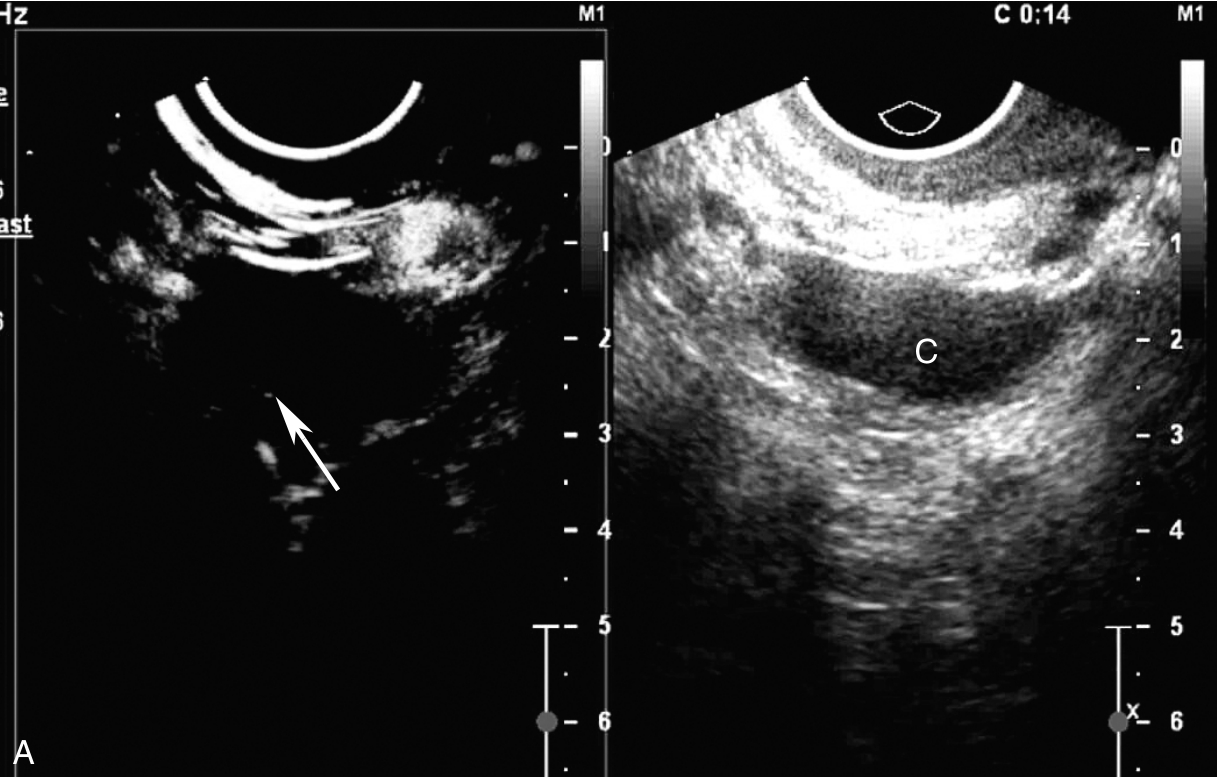

子宫经静脉超声造影见图3-12-3及ER 3-12-1。注入造影剂后16s,子宫内膜开始出现增强(图3-12-3A箭头所示),晚于子宫肌层增强;注入造影剂后23s,子宫内膜呈等增强,造影剂分布不均匀(图3-12-3B箭头所示),其周边出现造影低增强区;注入造影剂后42s,子宫肌层未见异常造影剂聚集(图3-12-3C箭头所示),子宫内膜消退与子宫肌层同步。

图3-12-3 子宫经静脉超声造影声像图

A.注入造影剂后16s;B.注入造影剂后23s;C.注入造影剂后42s。UT:子宫;EN:内膜。

子宫内膜样腺癌病灶的经静脉超声造影有如下特点:①子宫内膜增强呈“慢进同出”,未表现出高代谢的造影表现,分析可能与患者刚行宫腔诊刮且病灶仅侵及浅表肌层有关,故病灶较小且不典型;②局部内膜呈等增强,其周边出现造影低增强区,提示内膜增强不均匀;③子宫肌层未见异常造影剂聚集,提示肌壁无浸润。典型的子宫内膜癌造影表现为“快进慢出”的高增强,并可观察到内膜与子宫肌层界限不清。综上,该病例没有典型子宫内膜癌的高代谢造影表现,分析与患者刚行宫腔诊刮且病灶仅侵及浅表肌层有关。